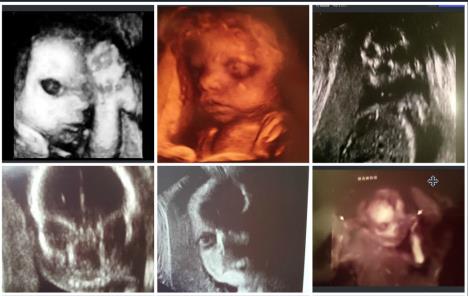

Kada buduće mame odu na ultrazvuk, jedva čekaju da im doktori daju slike njihove nerođene bebe kako bi uživale dok gledaju svog mališana.

Međutim, neke slike sa ultrazvuka zalede krv u venama. Kao da su izašle iz najgoreg horor filma.

1. Izgleda jezivo kad te beba iz stomaka gleda razgoračenih očiju.

2. Ovo nije beba, ovo je noćna mora!

3. Ova beba je skoro pa odrastao čovek.

4. Nešto nam govori da ova beba neće biti tako mirna.

5. Pozdravite se sa jezivim "kosturom"!

6. Beba koja izgleda kao da vrišti na vas...

7. Ovi roditelji, kada su otišli na 4D da vide svoju nerođenu bebu, nisu očekivali da će ugledati...

8. Nikome se nije dopao osmeh ovog dečaka.